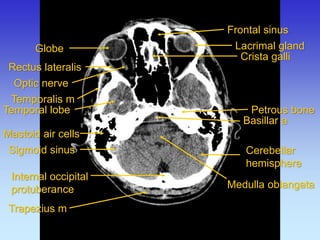

Frontal sinus

Lacrimal gland

Mastoid air cells

Medulla oblangata

Petrous bone

Rectus lateralis

Crista galli

Temporalis m

Temporal lobe

Cerebellar hemisphere

Trapezius m

Sigmoid sinus

Rectus medialis

Globe

Basillar a

Internal occipital protuberance

Optic nerve